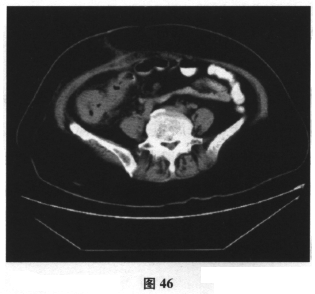

提示 辅助检查:血常规:WBC12.95×10

/L,N93%;腹部B超:右下腹见一均质回声区,范围为6.3cm×4.1cm,以低回声团为主,内可见多个短条状强回声,后伴声尾征。CT:升结肠起始段肠壁明显不规则增厚,肠腔变窄。腹部CT见图46。首先应考虑的并发症是( )